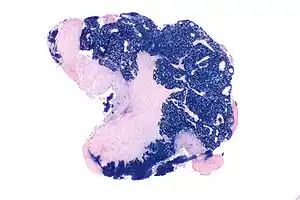

| Micrograph showing a nasopharyngeal carcinoma positive for Epstein-Barr virus-encoded small RNAs (EBER). | |

Undifferentiated nasopharyngeal carcinoma—high power[[ -